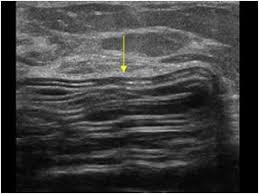

Stepladder sign: The collapsed shell is seen within the gel; this is one of the most reliable ultrasound signs of intracapsular rupture.

Subcapsular line sign: a thin line parallel to the capsule representing a minimally collapsed shell/leak within the capsule.

A high-frequency probe is used to survey the implant systematically in multiple planes, tracking the shell interfaces and looking for internal shell fragments or lines.